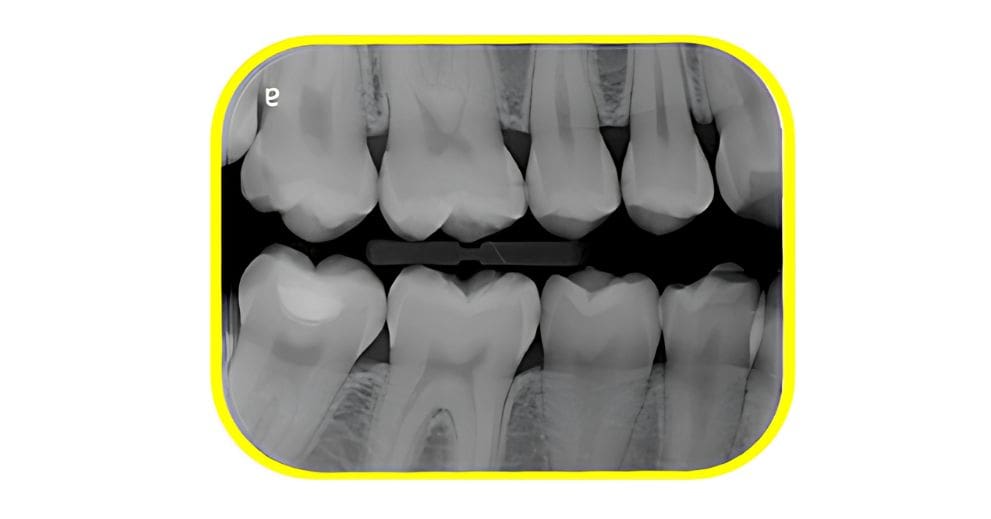

Sensors can be limiting. The active area of a rigid sensor is much smaller due to the sensor housing and cut corners. Whereas, ScanX PSPs provide a larger region of interest, ensuring a more accurate diagnosis the first time.